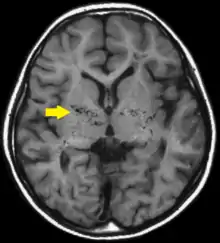

داء مويامويا (بالإنجليزية: Moyamoya disease) هو مرض نادر يحدث فيه ضيق في شرايين محددة بالمخ، مما يتسبب في إعاقة تدفق الدم بها نتيجة لذلك وأيضاً نتيجة لتكون الخثرات في داخلها.[1] يترتب على ذلك نمو لشرايين جانبية بجانب الشرايين المغلقة (دورة دموية رديفة) كي تقوم بتعويض نقص تدفق الدم للمخ، لكن هذه الشرايين الجديدة تكون ضعيفة وصغيرة، بالإضافة لذلك فإنها تكون معرضة لحدوث خثرات بداخلها أو تعرضها للنزيف أو التمدد. عند تصوير الأوعية الدموية باستخدام الأشعة السينية تظهر هذه الشرايين الجانبية على هيئة "نفخة الدخان" (باليابانية "もやもや" "مويامويا").[1][2]

يتم تشخيص المرض بشكل رئيسي من خلال الأشعة المقطعية على المخ، الرنين المغناطيسي، أو تصوير أوعية المخ.[6] تشير دراسة أجريت عام 2015 إلى امكانية ربط واصمات حيوية بالإصابة بالمرض.[7]